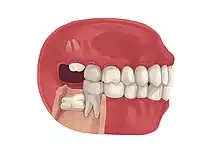

Impacted 2nd molar (red arrow) with developing wisdom tooth (green arrow)

There is no standard to screen for wisdom teeth. It has been suggested, absent evidence to support routinely retaining or removing wisdom teeth, that evaluation with panoramic radiograph, starting between the ages of 16 and 25 be completed every 3 years. Once there is the possibility of the teeth developing disease, then a discussion about the operative risks versus long-term risk of retention with an oral and maxillofacial surgeon or other clinician trained to evaluate wisdom teeth is recommended. These recommendations are based on expert opinion level evidence.[19] Screening at a younger age may be required if the second molars (the "12-year molars") fail to erupt as ectopic positioning of the wisdom teeth can prevent their eruption. Radiographs can be avoided if the majority of the tooth is visible in the mouth.